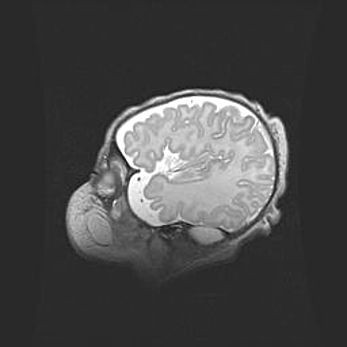

Лейкомаляция с кистозно-глиозной дегенерацией головного мозга.

Возраст: 2 месяца 25 дней

Вес: 6400 г

Окружность головы: 40 см

Срок гестации: 41 неделя

Лейкомаляцию относят к ишемически-гипоксическим повреждениям головного мозга, диагностируемым у новорожденных. При лейкомаляции в головном мозге обнаруживают очаги некроза, возникшие после тяжелой гипоксии и нарушения кровотока. В процессе морфогенеза очаги проходят три стадии: 1) развития некроза, 2) резорбции и 3) формирования глиозного рубца или кисты. Перивентрикулярная лейкомаляция (ПЛ) встречается примерно в 12% случаев среди новорожденных, обычно – у недоношенных детей, причем, частота ее зависит от массы, с которой младенец появился на свет. Наибольшее число малышей страдает лейкомаляцией, если масса при рождении 1500-2500 г.